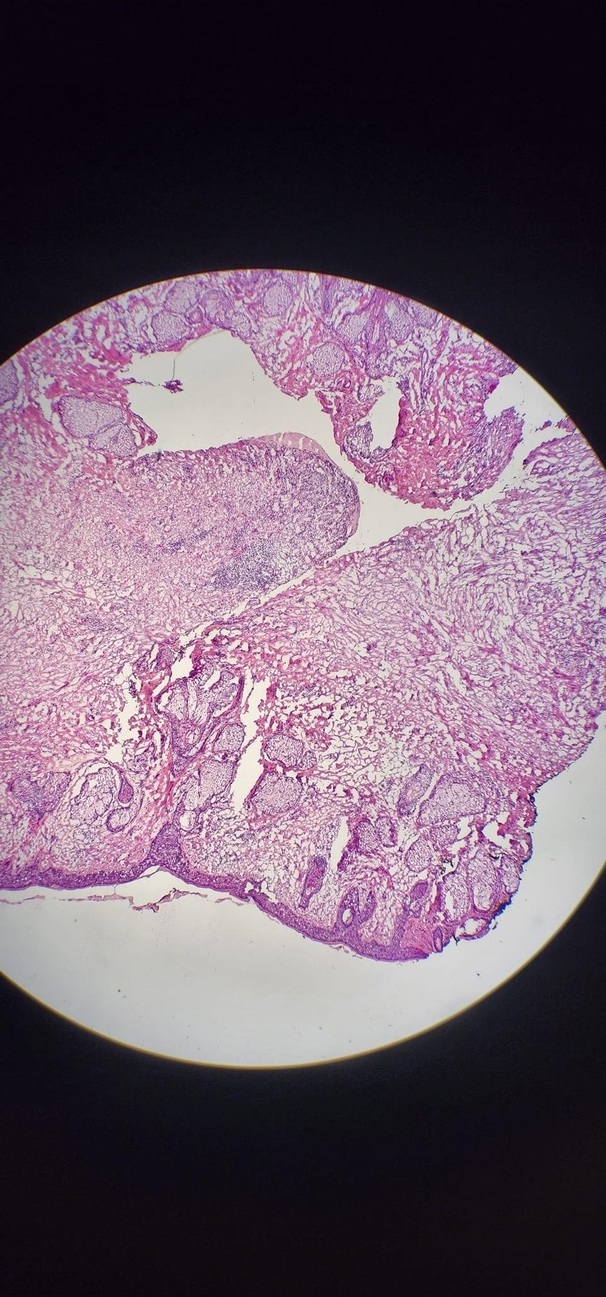

— Припустимо, ми маємо справу з утворенням на обличчі. Під місцевою анестезією ми видаляємо утворення із мінімальним захопленням зовні не зміненої шкіри. Невидиме утворення може бути набагато більшим за те, що лікар може діагностувати дерматоскопом. Тому видалена частина віддається гістологу, який оперативно проводить аналіз у той час, поки пацієнт ще лежить на операційному столі. Гістолог каже, чи є у краях на вигляд здорової шкіри залишки пухлини. Про результати каже хірургу. Перш ніж віддати зразок гістологу, його помічають, і хірург чітко знає, де є сліди онкології, і робить повторне висічення за необхідності. Потім процедура повторюється до того часу, поки краї висіченої тканини не будуть «чистими». І буває так, що потрібно зробити 3-5 висічень. Ми починаємо з маленької ранки, а можемо закінчити великим шкірним дефектом.

За такого підходу рецидив становить 1-3%. Якщо ж видалити лише видиме новоутворення без інтраопераційного гістологічного аналізу чистоти країв резекції, рецидив становить 18-34%. На цьому місці через кілька років може з’явитися нове утворення, і великий ризик, що воно пошириться глибше, і вимагатиме вже іншого серйознішого лікування.

По суті, гістолог дає нам відповідь на три питання: перше – це верифікація пухлини; друге – чистоту країв; третє – глибина проростання утворення. Якщо меланома проникає у глибину до 0.8 мм – це поверхнева меланома і після висічення лікування вважається закінченим. Якщо глибина поразки більша, то за протоколом далі робиться біопсія сторожового лімфовузла. Якщо цікаво, теж можу докладніше про це розповісти.